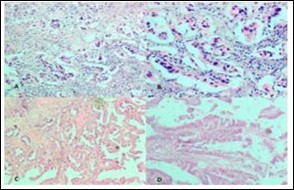

Figure 2.Photomicrograph showing A, cib;k%=Ss in low power; B, High power view of CiNk%=1%us showing lipid laden macrophages; C,ggtj of Gall Bladder; D, Pyloric Metaplasia Gall Bladder (H&E)

Figure 3.Photomicrograph showing A, Low power view of Adenocarcinoma Gall bladder; B, High power view shows attempted gland formation with moderate pleomorphismmoderately differentiated adenocarcinoma Gall Bladder; C, Low power view of Papillary carcinoma GB; D, High power view showing papillae with fibrovascular cores lined by malignant cells- Papillary carcinoma GB (H&E)